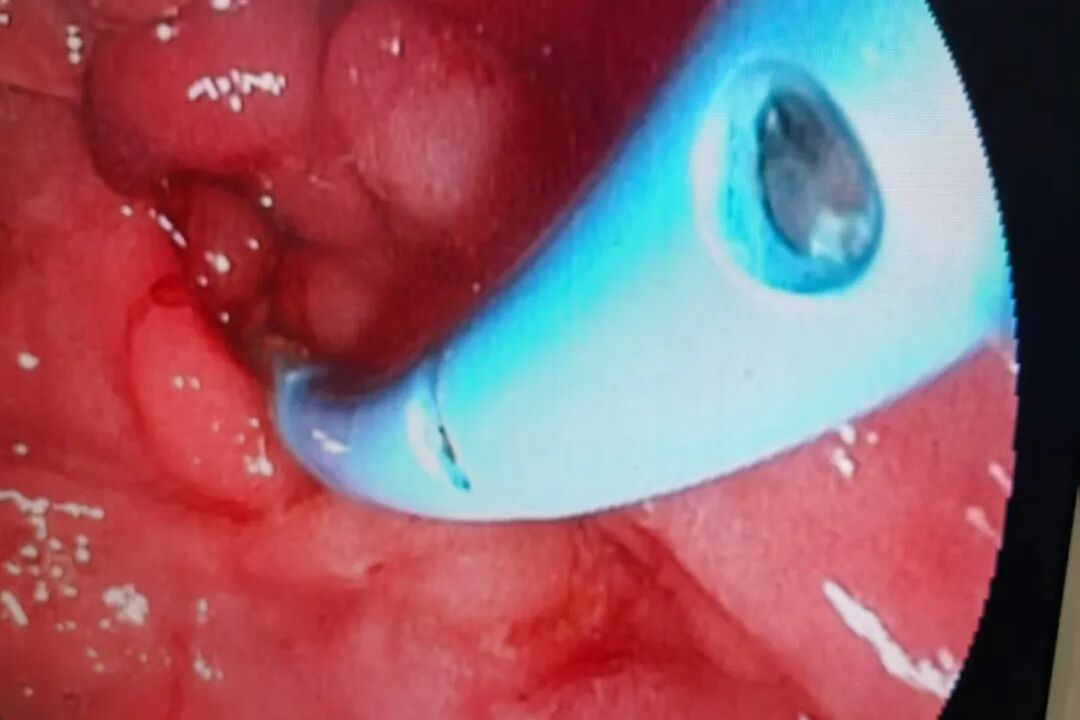

患者的救治刻不容缓!消化内科ERCP团队与介入室紧密协作,以最快速度安排患者行急诊ERCP取石术。术中,患者的情况给ERCP团队带来重重挑战,进镜达患者胃底时发现胃腔有大量食物潴留,患者幼年胆道手术史更让手术难度大大提升。叶营主任医师借娴熟精湛的内镜技术,沉着应对、精准操作,成功克服难题,顺利完成ERCP取石治疗,解除了患者的胆道梗阻。术后患者恢复良好,各项指标逐步恢复正常,顺利出院。出院前,患者以赠送锦旗的形式来表达对消化内科团队的诚挚谢意,同时也是对消化内科团队技术和服务的充分肯定。